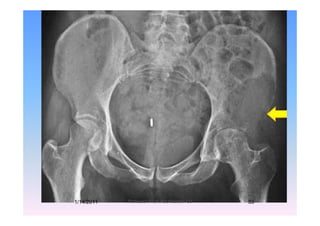

3 Periacetabular lesions3-Periacetabular lesions

T h l i l d h i lifi d thTechnological advances have simplified the

surgical treatment of Pelvic Metastasesg

Class III 55 Y, Male, RCC

M di l ll i d d h f thMedial wall, superior dome and much of the

acetabular rim have been destroyed

(Preserved femoral head)1/14/2011 49Professor Freih AbuHassan -UJ